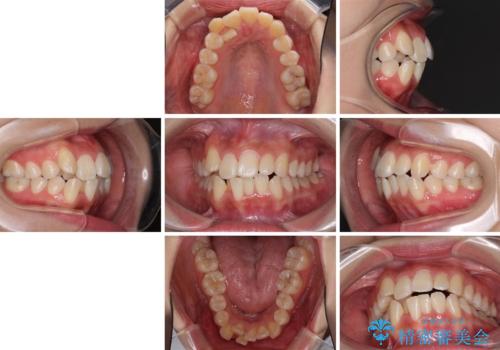

前歯の正中のズレを改善 目立たないワイヤー装置での抜歯矯正

- 八重歯を気にして来院された患者様です。

上下ともに前突感と叢生が認められ、上顎の正中が著しく右側にずれていたため、上下左右第一小臼歯4本を抜歯し、ワイヤー矯正にて治療を行うこととしました。

移動量が多かったため、治療期間は通常より半年~1年ほど長くかかりましたが、上下の正中をほぼ同じ位置にまで移動させることができました。